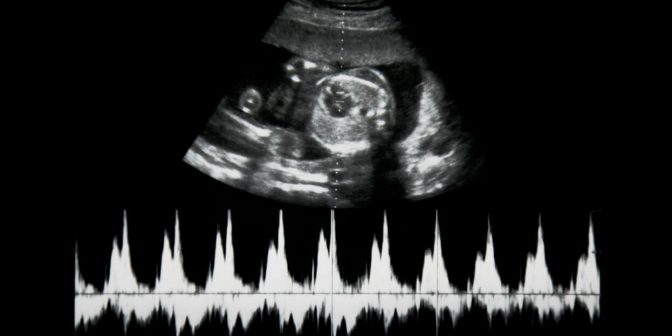

Bantuan Prediksi Kelahiran Dengan Ultrasonografi

Biasanya untuk perkiraan lahiran, banyak para ibu yang tidak menggunakan layanan ultrasonografi, yang dapat memberi tahu tanggal persalinan yang akurat. Sebelum menjalani ultrasonografi, dokter akan memastikan, apakah jika siklus haid normal, dan memastikan umur ibu hamil apakah berusia 30 lebih.

Dengan mengetahui itu, dokter tidak akan ragu untuk menjalankan ultrasonografi, karena informasi tersebut membantu untuk mendapatkan hasil yang lebih akurat.

Namun, cara prediksi dengan ultrasonografi, sangat tidak dianjurkan oleh dokter manapun, jika ibu memiliki histori keguguran maupun juga komplikasi kehamilan.

Perkiraan Dengan Mendeteksi Detak Jantung Bayi

Untuk cara ini, biasanya dokter yang akan memeriksanya, dan perkiraan lahiran ini diketahui dengan mendengar detak jantung bayi pertama kali. Dengan metode ini pun, dokter bisa menentukan hari perkiraan lahir bayi ibu, hanya mendengar detak jantung bayi tanpa menghitung manual.

Pada umumnya, detak jantung bayi akan terdengar pada sekitar minggu ke 9-10, atau ketika ibu merasakan gerakan janin pertama kali. Gerakan janin sendiri, biasanya akan mulai terdeteksi antara usia kehamilan 18-22 minggu, bisa juga lebih awal atau juga lebih lambat.